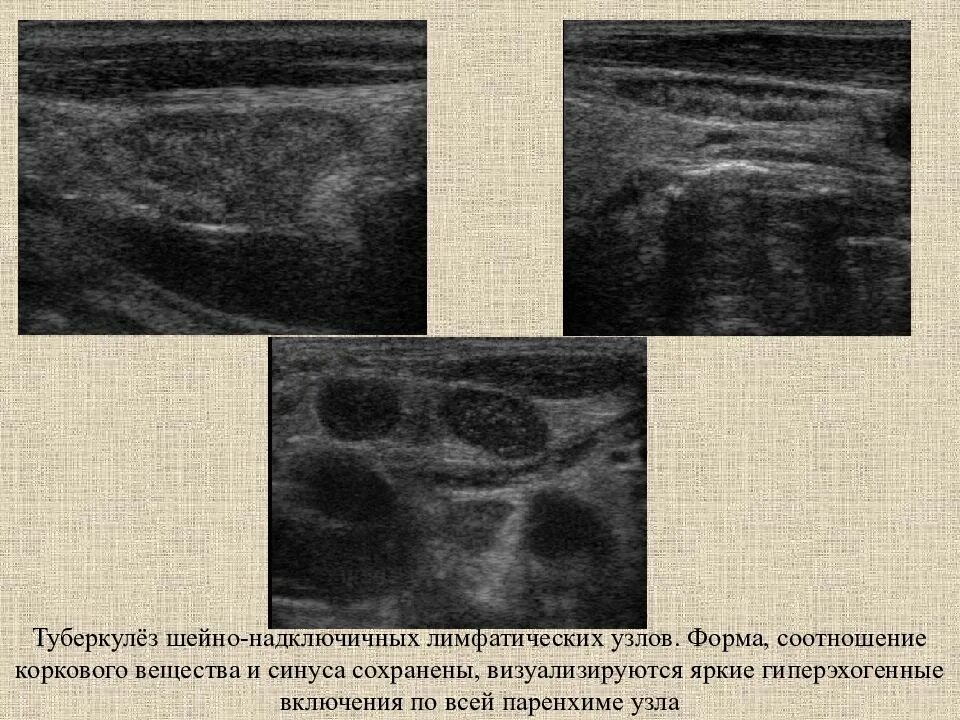

Обследование лимфоузлов